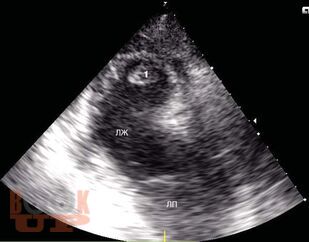

Рассмотрены основные режимы трансторакального эхокардиографического исследования, методика выведения стандартных эхокардиографических позиций, методика основных измерений структурно-функциональных показателей деятельности сердца.